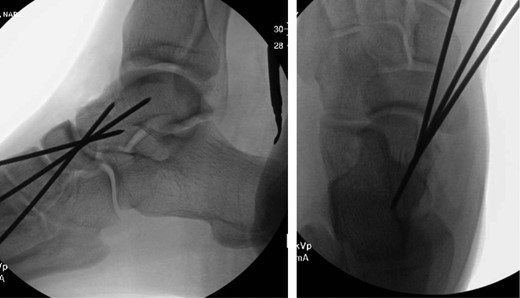

Once general anesthesia was induced, closed reduction was attempted using axial traction with the knee in flexion. Closed reduction was unsuccessful once again (Fig. 3) so the decision was made to attempt open reduction. An anteromedial approach was used dissect down to the talonavicular joint. Retractors were placed with care to avoid injury to tibialis anterior tendon or superficial peroneal nerve. The joint capsule was seen to be disrupted and further exposure revealed a thin, coronal fracture of the anteromedial aspect of the talar head measuring roughly 2 cm in length and 6 mm in thickness (Fig. 4). Once this fragment was removed, the subtalar and talonavicular joints were easily reduced. It was thought that this incarcerated fragment was the likely cause for the unsuccessful closed reduction. The talar head fragment was unamendable for stabilization due to its small size with poor healing potential, thus it was removed. The talonavicular joint was then percutaneously pinned in retrograde fashion with three K-wires (Fig. 5) to maintain anatomic reduction of the subtalar and talonavicular joints and the foot was splinted. At 2 weeks follow-up the patient was doing well and radiographs revealed no interval loss of reduction (Fig. 6).